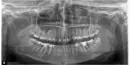

Также на 6 внизу на снимке показано, что есть воспаление (10 лет назад нервы удалены, каналы запломбированы), побаливает при жевании твердой пищи и ноет периодически. Также на некоторых других зубах есть кариес.

Восьмые зубы необходимо удалить все, можно оставить только 48, он стоит в зубном ряду и не создаёт скученность, и не страдает соседняя семерка. Во всех трёх остальных случаях Ваши зубы мудрости необходимо удалить как можно раньше.

На обеих нижних шестёрках имеется хронический воспалительный процесс обширных размеров, и если Вы незамедлительно не займётесь лечением, то вскоре мы получим капсулированную кисту, и как следствие, удаление.

Также много проблем, связанных с неправильным контактом между зубами.

Последовательность лечения неважна, главное оперативно начинать лечение.